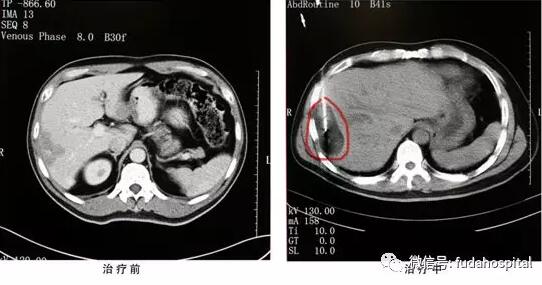

Семья г-на Лю и его друзья считали, что не обязательно ехать в Китай для химиотерапии. Однако совет врача из Онкологической больницы Фуда придал ему уверенности и заставил его решительно пойти в Китай. 21 октября этого года г-н Лю поступил в Онкологическую больницу Фуда. Группа экспертов во главе с директорм Ню Личжи разработала план лечения при своей консультации. Через четыре дня г-н Лю провел биопсию опухоли печени и аргон-гелиевую криоаблацию.

Аргон-гелиевая криоабляция - это новый метод минимально инвазивного лечения. Это не настоящий «нож». Хирургия требует только местной анестезии в месте пункции. Во время операции нет явного дискомфорта, поэтому не требуется общий наркоз. Под контролем цветного ультразвукового допплера опухоль печени использовалась в качестве целевой области, криозонд через место прокола достигает целовой области. После сканирования КТ она была заморожена в течение 15 минут и двух циклов. КТ показала, что замороженный шар покрыл целевую область и был удален после повторного нагревания. Затем перевязал место прокола, и только 2 мл кровоизлияния во время операции. С момента создания Онкологической больницы Фуда группа по аргон-гелиевой криотерапии во главе с вице-директором Ню Личжи лечила более 10 000 случаев опухолей, поэтому Международное общество криотерапии оценило Онкологическую больницу Фуда как учебный центр криотерапии в Азиатско-Тихоокеанском регионе.